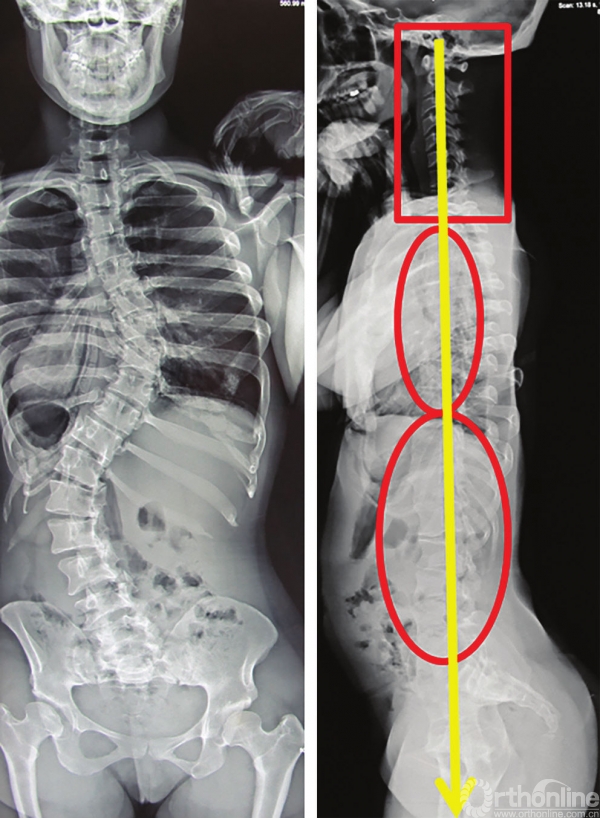

向上力线解释了合并颈椎后凸的特发性脊柱侧弯患者,通常合并有平背表现(图3-36)。

图3-36 特发性脊柱侧弯“平背”患者的脊柱力线,颈椎呈后凸状态